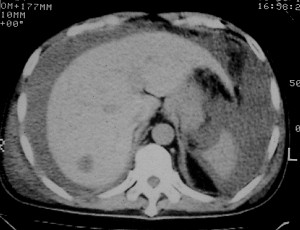

右侧肺癌术后:肝内可见多个大小不等的低密度结节影。腹腔及双侧胸腔大量积液。考虑:肺癌并胸膜及肝脏转移。

腹水,肝及右肾多发低密度影。考虑转移。

肝及右肾转移瘤,双侧胸水

右肾及肝内多发转移瘤,胸水。

1、右肺癌术后改变。2、双侧胸水、腹水。3、多发性肝囊肿,右侧肾囊肿。